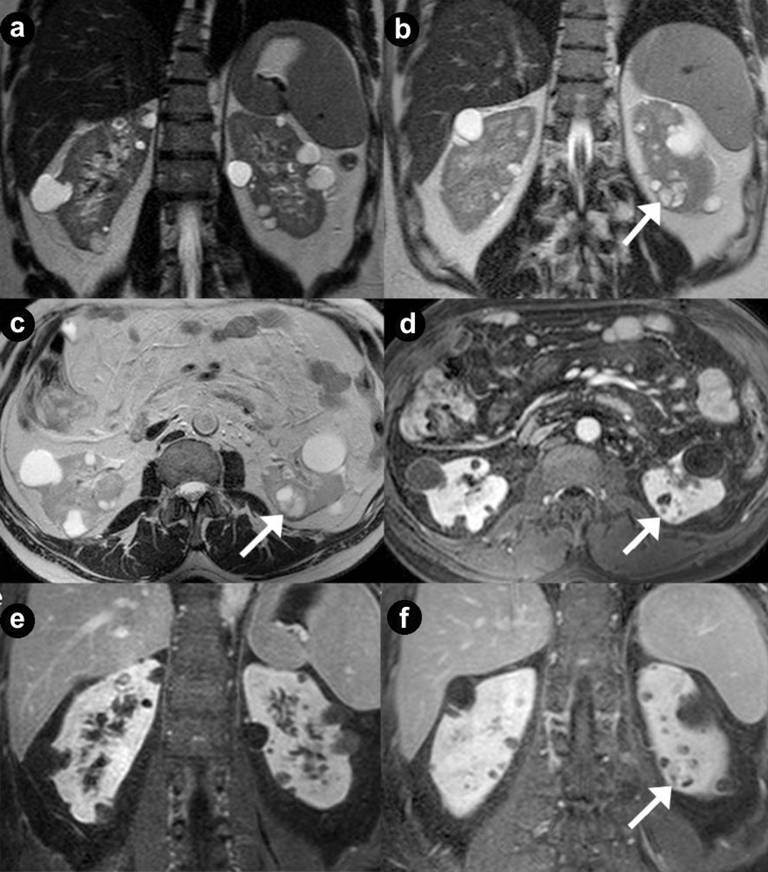

Figure 4. Pancreatic diffuse microcystic serous cystadenoma and pancreatic non functioning neuroendocrine tumor in the same patient. A 24-year-old woman with VHL disease and symptoms of pancreatic exocrine insufficiency. Axial (a. b.) and coronal (c.) T2-weighted MR images, MR cholangiopancreatography (d.) and axial 3D volumetric gradient-echo T1-weighted fat suppressed images after intravenous contrast medium administration during arterial pancreatic (e.) and portal venous (f.) phases of contrastographic dynamic study. Pancreatic gland is enlarged and parenchyma is completely replaced by multiple, lobulated fluid cysts, hyperintense on T2-weighted MR images, with a “bunch of grapes” pattern (a. b. c. d.). In the pancreatic head, a round solid mass (arrow), with the signal intensity less high than other pancreatic cysts on T2-weighted MR images and homogeneous enhancement after intravenous contrast medium administration during arterial pancreatic phase (e.), with low wash-out in portal venous (f.) phase, is present. Multiple bilateral renal cystic lesions and large complex mass on the left kidney (short arrow), with fluid signal intensity, multiple solid septa and heterogeneous enhancement after intravenous contrast medium administration during arterial (e.) and portal venous (f.) phases, are detected. Total pancreatectomy and surgical enucleation of the left renal mass were performed. Histological specimen showed the presence of pancreatic diffuse serous cystadenoma, non functioning neuroendocrine tumors of pancreatic head and cystic renal cell carcinoma of left kidney. |

Figure 5. Pancreatic diffuse microcystic serous cystadenoma and pancreatic non functioning neuroendocrine tumor in the same patient. Asymptomatic 34-year-old woman, member of family affected to VHL disease. Axial (a.) and coronal (b.) T2-weighted MR images, MR cholangiopancreatography (c.) and axial 3D volumetric gradient-echo T1-weighted fat suppressed images after intravenous contrast medium administration during arterial pancreatic (d.), portal venous (e.) and delayed (f.) phases of contrastographic dynamic study. Pancreatic gland is enlarged and parenchyma is completely replaced by multiple, lobulated fluid cysts, hyperintense on T2-weighted MR images, with a “bunch of grapes” pattern (a. b. c.). The wall of cystic lesions and septa inside them shows enhancement after intravenous contrast medium administration during arterial pancreatic (d.), portal venous (e.) and delayed (f.) phases. In pancreatic head and neck, some cysts result so small and so numerous as they show lower signal intensity on T2-weighted MR images compare to fluid lesions and appear at MR imaging like solid mass (short arrow). In the pancreatic body, a round solid mass (arrows), with the signal intensity less high than the other pancreatic cysts on T2-weighted MR images and homogeneous enhancement after intravenous contrast medium administration during arterial pancreatic phase (d.) with low wash-out during portal venous phase (e.) but hypointense on delayed (f.) phase, is present. Multiple bilateral renal fluid cysts are detected. Splenopancreatectomy was performed. Histological specimen showed the presence of pancreatic diffuse serous cystadenoma and non functioning neuroendocrine tumors of pancreatic body-tail. |

Thirty-four pancreatic lesions were found in the 23 patients. In qualitative analysis, the MR imaging findings were: 6 (26.1%) unilocular fluid cystic lesions (Figure 1abc): 3 (13.0%) in pancreatic head, 3 (13.0%) in pancreatic body-tail; 11 (47.8%) serous micro- or micro/macro-cystic cystadenomas (Figures 1def, 4, and 5): 1 (4.3%) in pancreatic head, 2 (8.7%) in pancreatic body-tail (Figure 1), 8 (34.8%) diffuse (Figures 4 and 5); 8 (34.8%) neuroendocrine solid tumors: all of them non-functioning NET and hypervascular during arterial pancreatic phase of contrastographic dynamic study (Figures 2, 3, 4, and 5), 4 (17.4%) at pancreatic head (Figures 2ab; 3ace, and 4), 4 (17.4%) at pancreatic body-tail (Figures 2cd and 5); 1 (4.3%) cystic non-functioning NET, diffuse in all pancreatic gland (Figure 6); in 4 (17.4%) cases association of non-functioning NET and pancreatic cystic lesions (3 cases of association of non-functioning NET and serous cystadenoma (13.0%); 1 case of association of non-functioning NET and pancreatic simple cystic lesion (4.3%)) were present (Figures 4 and 5). Vascular invasion was not detected in any patients.

Microcystic serous cystadenomas or micro/macro-cystic serous cystadenoma may be diffuse in all pancreatic gland [22, 23]. In this case the pancreas appears at MR imaging [23] markedly enlarged, with parenchyma almost completely replaced by innumerable cysts, with “bunch of grapes” pattern, present only in these patients (Figures 5 and 6).

To obtain pathological specimen and histological confirmation of MR imaging findings we retrospectively evaluated symptomatic patients only (13 out of 23; all of them submitted to surgical procedure) and we do not know the pathological specimen of the remaining patients not submitted to surgical procedure(10 out of 23). It can explain the high frequency of serous cystadenoma in our series of VHL patients, differently from other study cases. The average maximum diameter of these lesions was 56.6 mm and 34.8% of these cases were diffuse in all pancreatic gland (Figures 4 and 5); 8.7% were localized at pancreatic body-tail (Figure 1def) and 4.3% were localized at pancreatic head (Figure 3bdf). According to Agarwal et al. [22], in 13.0% of our cases, the serous cystadenoma (all of them diffuse in all pancreatic gland) were associated to hypervascular solid neuroendocrine tumors (Figures 4 and 5).

In our series of VHL patients, solid pancreatic NETs were present in 34.8% of cases, all non functioning and hypervascular during enhanced pancreatic arterial phase of MR dynamic study (Figures 2, 3, 4, and 5). As mentioned above, to know pathological specimen and histological diagnosis in order to confirm MR imaging findings, we included symptomatic patients only (13 out of 23) in our retrospective review, all of them submitted to surgical procedure. We do not know the pathological specimen of the remaining patients not submitted to surgical procedure(10 out of 23). This can explain the highest frequency of NETs in our series of VHL patients, compared to other study cases.

At MR imaging [3, 4, 9, 15, 16, 38, 39, 40] they result hypointense on T1-weighted images, and hyperintense on T2-weighted images (Figures 4ab, 5a, and 7abc), with no walls enhancement after intravenous gadolinium contrast medium administration (Figures 5def and 7def).

According to the literature, in our series simple renal cysts were present in 78.3% of patients. In 69.6% of our cases they were multiple and bilateral (Figures 4ab, 5, and 7).

Complex cysts were present in 56.5% of VHL patients (Figures 1a and 2b). The average maximum diameter of lesions was 50.5 mm in simple cysts and 60 mm in complex cysts.